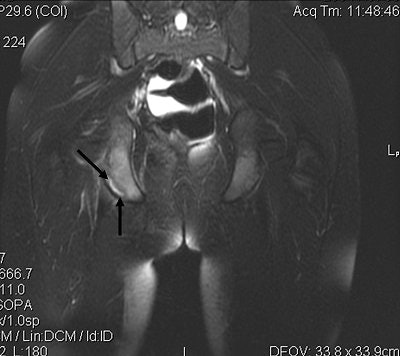

![]() |

| Figure 3. Coronal T2-weighted MR image of the pelvis demonstrates increased signal intensity at the avulsion site on the right ischial tuberosity (black arrows). |